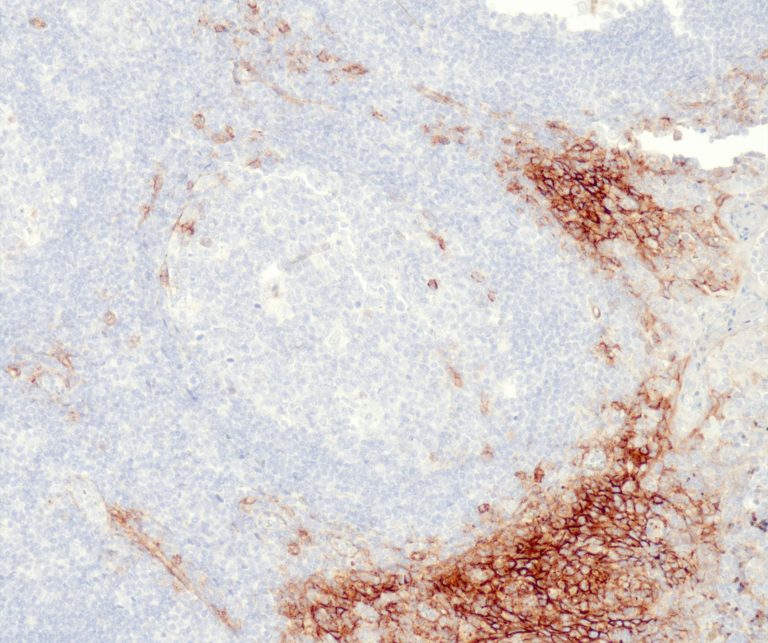

Vascular Pathology

Gastrointestinal (GI) Pathology

General Marker

Breast Pathology

Endocrine Pathology

Gynecological Pathology

Neuropathology

Infection Markers

Lung Pathology

Urinary Tract Pathology

Transplantation Pathology

Soft Tissue Pathology

Hematopathology